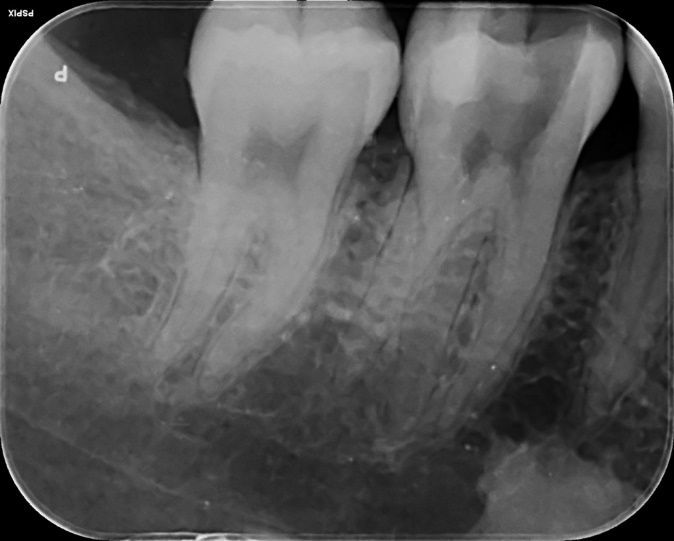

Lower Molar and premolar Primary root canal treatment